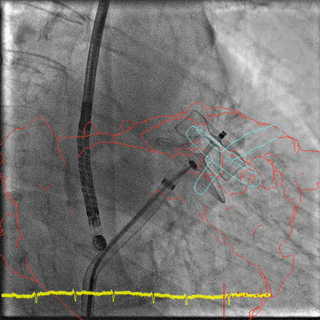

TMVR

- Cvi42 Mitral, distribuito da GE per Circle Cardiovascular, è un'applicazione leader che offre un set di strumenti e un flusso di lavoro completi per la valutazione della valvola mitrale. Accessibile solo su AW 4,7. Cvi mitral è venduto separatamente. Potrebbe non essere disponibile in tutti i mercati. Contattate il rappresentante commerciale locale

- 15596_MVQ_Whitepaper_v7.pdf